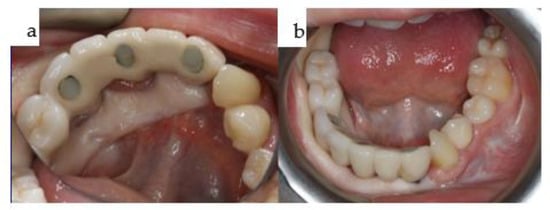

Figure 23. (ad): The two overdentures for the maxilla (a,c) and the mandible (b,d).